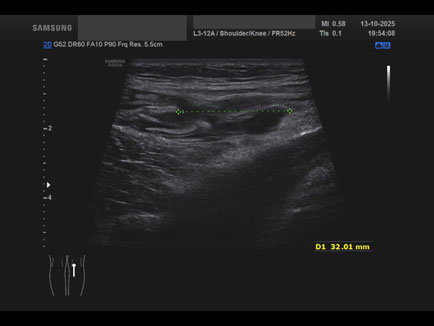

Data inserimento: 16/10/2025

Ecografia del: 13/10/2025

Strumento: Samsung

Sonda: Lineare

Commento all'esame: giovane atleta con referto di RMN che riporta cisti del semimembranoso/gemello e falda fluida lungo il gemello mediale medesimo.

Alla ETG:

A. formazione cistica di circa 22 x 17 x 23 mm (DAP x DT x DL = 4.5 ml) indovata tra il semimembranoso ed il gemello mediale: borsite dei tendini suindicati; assenza di falde fluide a carico dello sfondato sottoquadricipitale!

B. rottura completa del semitendinoso in sede distale con diastasi dei monconi di circa 25 mm.

Conclusioni: lesione e cisti del muscolo semitendinoso destro (right semitendinosus muscle injury and cyst).